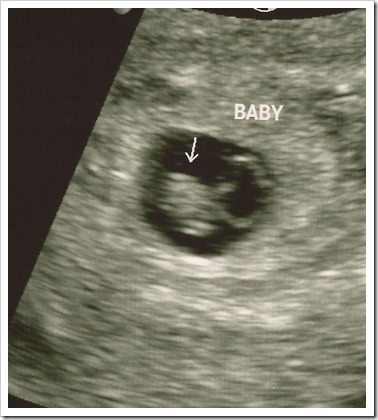

I went for my first pre-natal appointment on August 3 and saw the heartbeat and got a picture of the little bean.

angel 2_8.5.11_6wks3days